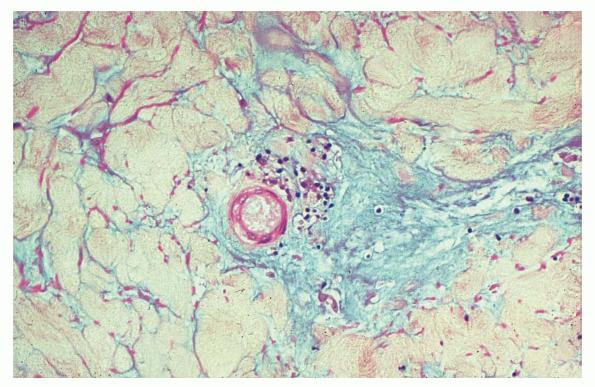

The classic lesion shows a wedge-shaped area of altered dermis covered by atrophic epidermis with slight hyper-keratosis. Dermal alterations may include frank necrosis. More common, however, are edema, extensive mucin deposition, and slight sclerosis . A sparse perivascular lymphocytic

infiltrate may be seen, although the dermis is largely acellular. Typically, vascular damage is noted in the vessels at the base of the “cone of necrobiosis.” Vascular alterations may be subtle and manifest as endothelial swelling or demonstrate lymphocytic vasculitis. However, more characteristically, intravascular fibrin thrombi may be noted, suggesting that the dermal and epidermal changes result from ischemia. Altered vessels may lack an inflammatory infiltrate. The histopathology observed may vary with the evolution of the lesions. Early lesions may be more mucinous and mimic tumid lupus, whereas more evolved lesions are more sclerotic and suggest lichen sclerosus et atrophicus (.